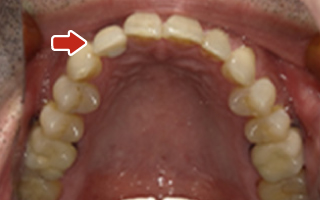

Before

After

| 45歳 男性 | 医療関係者紹介 |

|---|---|

| 主訴 | 右前歯が取れた(右上2) |

| 処置内容 |

1本インプラント埋入+再生療法 抜歯即時埋入⇒抜歯を行い、同時にインプラント埋入(即時埋入) |

| 治療費用 | 上顎: 約40万円(税込) |

| 治療期間 | 約11ヶ月 |

| リスク | 上部構造物、仮歯の破折、術後の腫れ(3日)、人工歯根脱落リスクがあります |